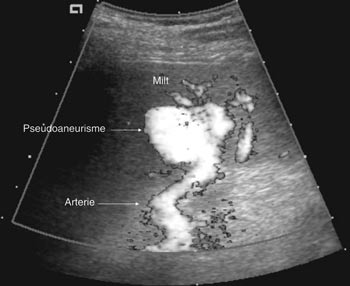

Pasient 2. En 20 år gammel mann ble utsatt for en trafikkulykke. Han var komatøs og ble intubert på skadestedet. CT-undersøkelse ved Ullevål universitetssykehus viste venstresidig pneumothorax og costafrakturer. I milten forelå en laserasjon kaudalt (skadegrad III), men normale funn i hilusnivå (e-fig 4). Pasienten ble observert og overflyttet til lokalsykehus etter tre dager. Seks dager etter traumet ble det gjort en CT-kontroll med arteriell kontrastfase. Denne viste en tilkommet, høytattenuerende lesjon ved milthilus, forenlig med et pseudoaneurisme (e-fig 5). Pasienten ble flyttet tilbake til Ullevål universitetssykehus hvor det ble utført angiografi med embolisering (e-fig 6). Ultralydkontroll samme dag viste opphørt sirkulasjon i lesjonen. Tre dager senere ble pasienten utskrevet.

Ultralydundersøkelse i traumesammenheng er vanlig ved oppfølging av kjente forandringer, spesielt hos barn (11). I akuttfasen finner vi det imidlertid vanskelig å benytte slik undersøkelse som grunnlag for skadegradering, og sensitiviteten er vanligvis for lav til at metoden kan benyttes som eneste undersøkelsesmodalitet ved stumpe buktraumer (12).